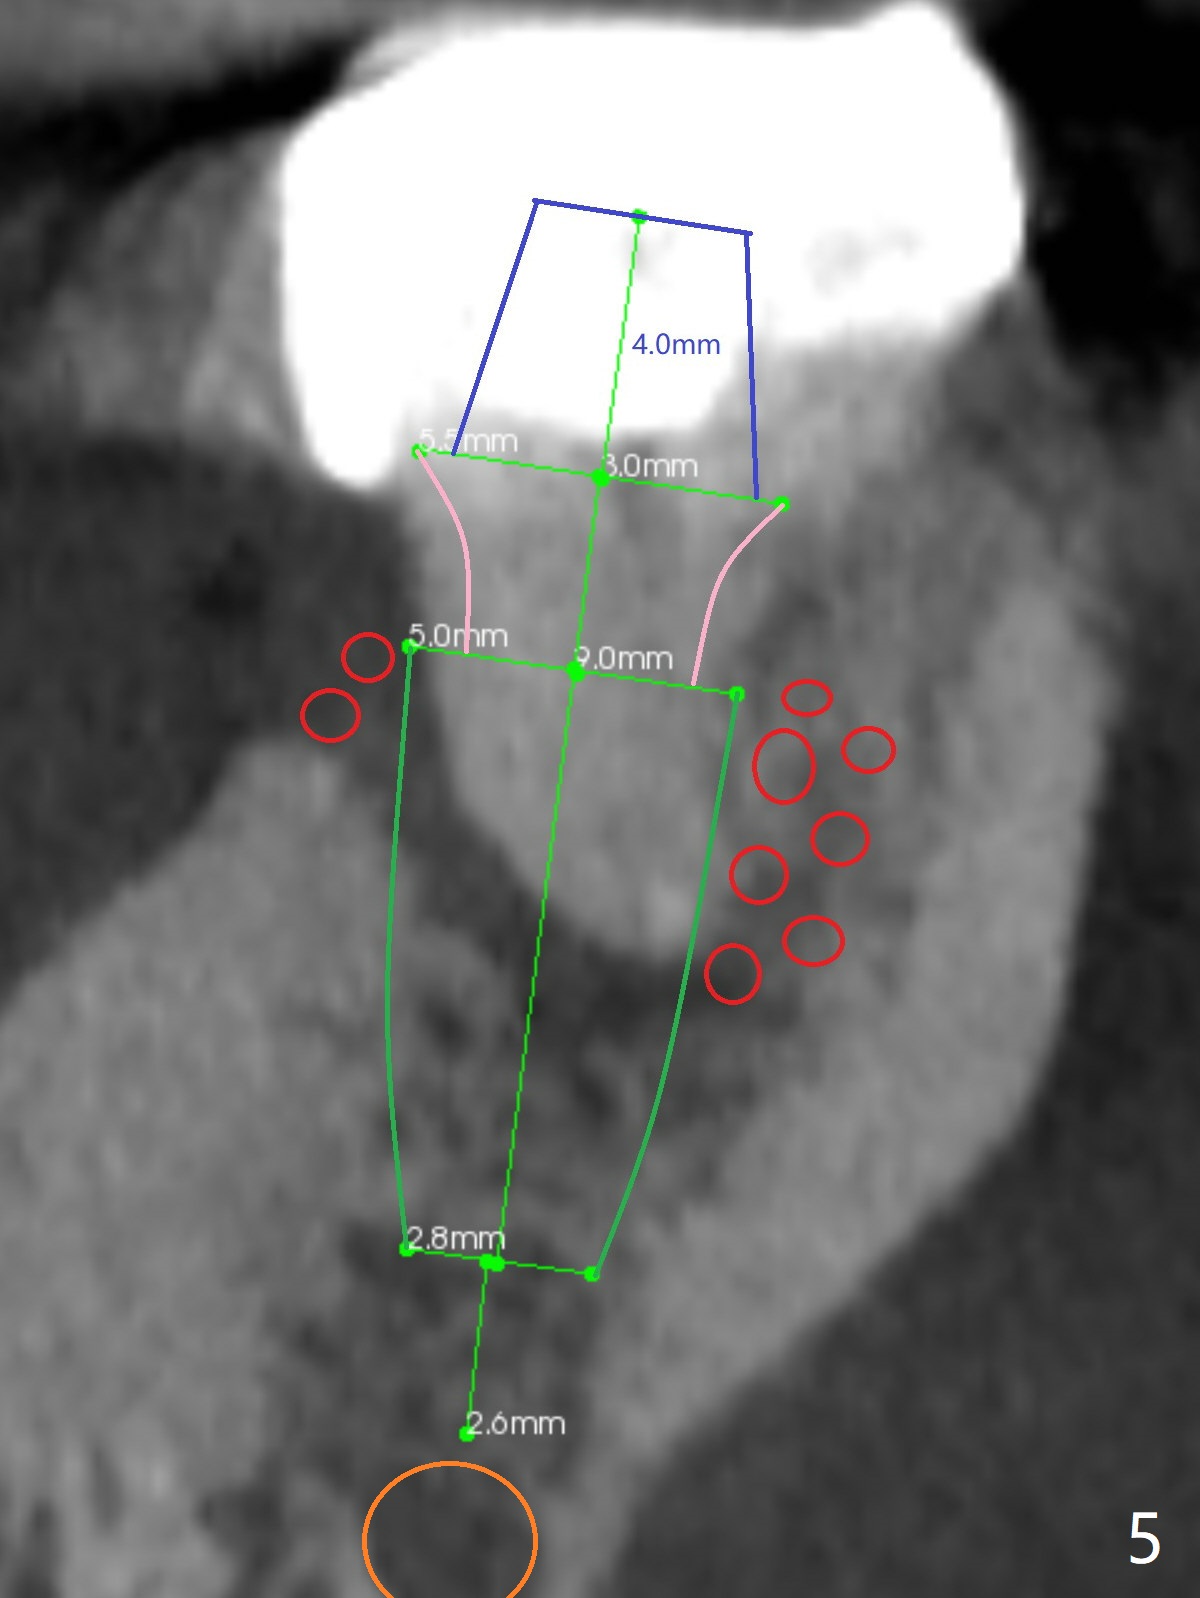

A 53-year-old man will return for #18 extraction and implant because of endo failure after the same treatment at #14 (Fig.1). It appears that the mesiolingual canal is missing for RCT (Fig.2 (coronal section at the mesial root)). Bony defect is buccodistal; try to place an implant as mesiolingual as possible (Fig.3 (axial section)). To reduce lingual (L) plate perforation and neuropathy (orange), the implant is expected to be 5-6x9 mm (Fig.4,5). Use 4 mm stopper from DIO Sinus Kit for osteotomy (Fig.1,4,5). If his vein is prominent, prepare PRF 1-2 tubes.